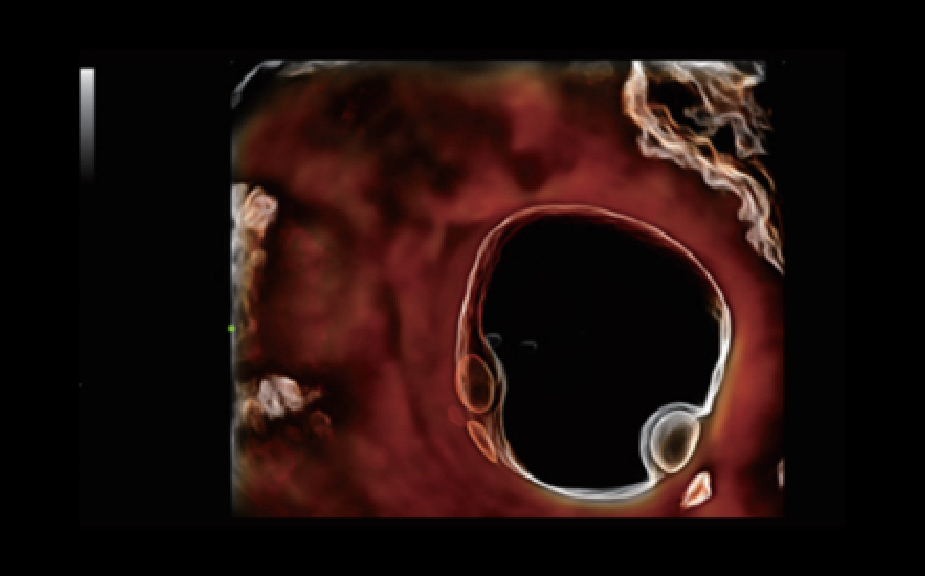

El sistema Nuewa I9, dise?ado exclusivamente para la atenciĂłn mĂ©dica neonatal y de mujeres, brinda una experiencia innovadora integral. Estas innovaciones se desarrollan sobre la base de un conocimiento profundo de situaciones clĂnicas complejas para proporcionar respuestas precisas y oportunas, una gran eficiencia y una experiencia de usuario extraordinaria.

SoluciĂłn completa con tecnologĂa de ZST +

La plataforma ZST+?es una innovaciĂłn extraordinaria que representa toda una evoluciĂłn en el ĂĄmbito de la ecografĂa. Transforma las mĂ©tricas ecogrĂĄficas de la formaciĂłn de haces convencional al procesamiento basado en datos de canal. Supera la limitaciĂłn tradicional de tener que equilibrar entre resoluciĂłn espacial, resoluciĂłn temporal y uniformidad del tejido, con lo que ofrece una calidad de imagen excepcional para soluciones de producciĂłn de imĂĄgenes infinitas con mejoras continuas.